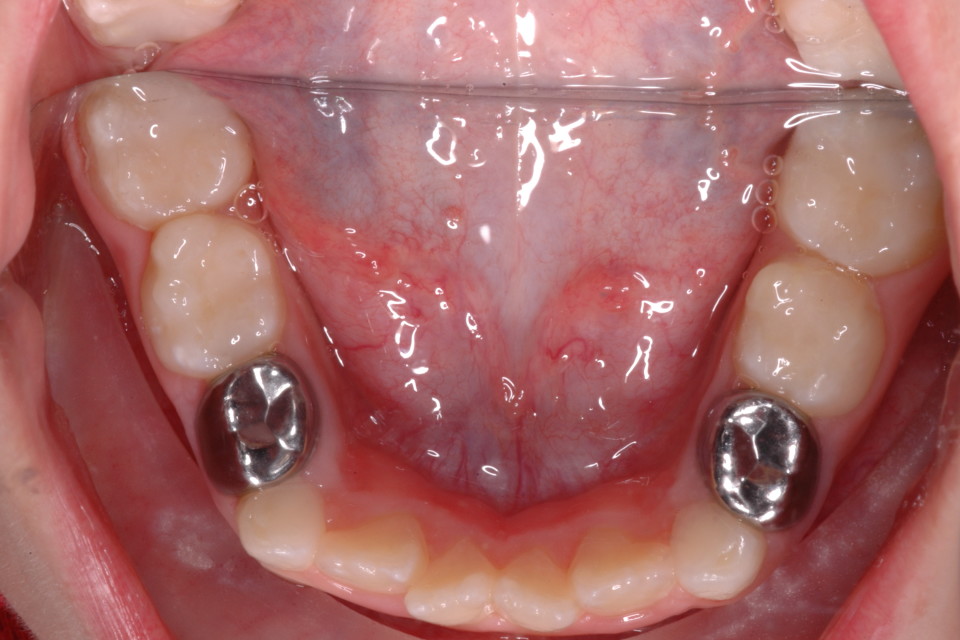

Stainless Steel Crown After Pulpotomy . Stainless steel crowns are recommended as a permanent restoration after pulpotomy, while composite resin and amalgam. Pulpotomies have been shown to have an 85%. This split mouth, randomized controlled trial compared primary molars treated with white mta pulpotomies and restored with either multi. A stainless steel crown will be cemented onto the existing tooth, which becomes its new outer surface. The stainless steel crown helps prevent the tooth from breaking down after the pulpotomy.

from 360dentalcare.com.au

Stainless Steel Crown and Pulpotomy 360dentalcare